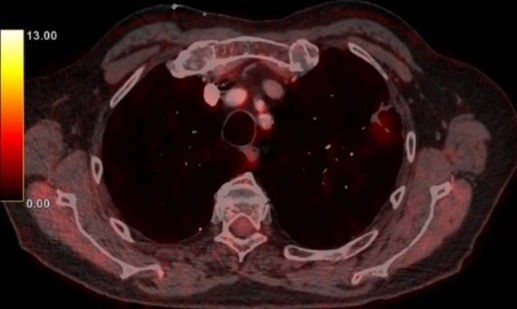

Man, 74 år

Vilken behandling är att rekommendera i nuläget?